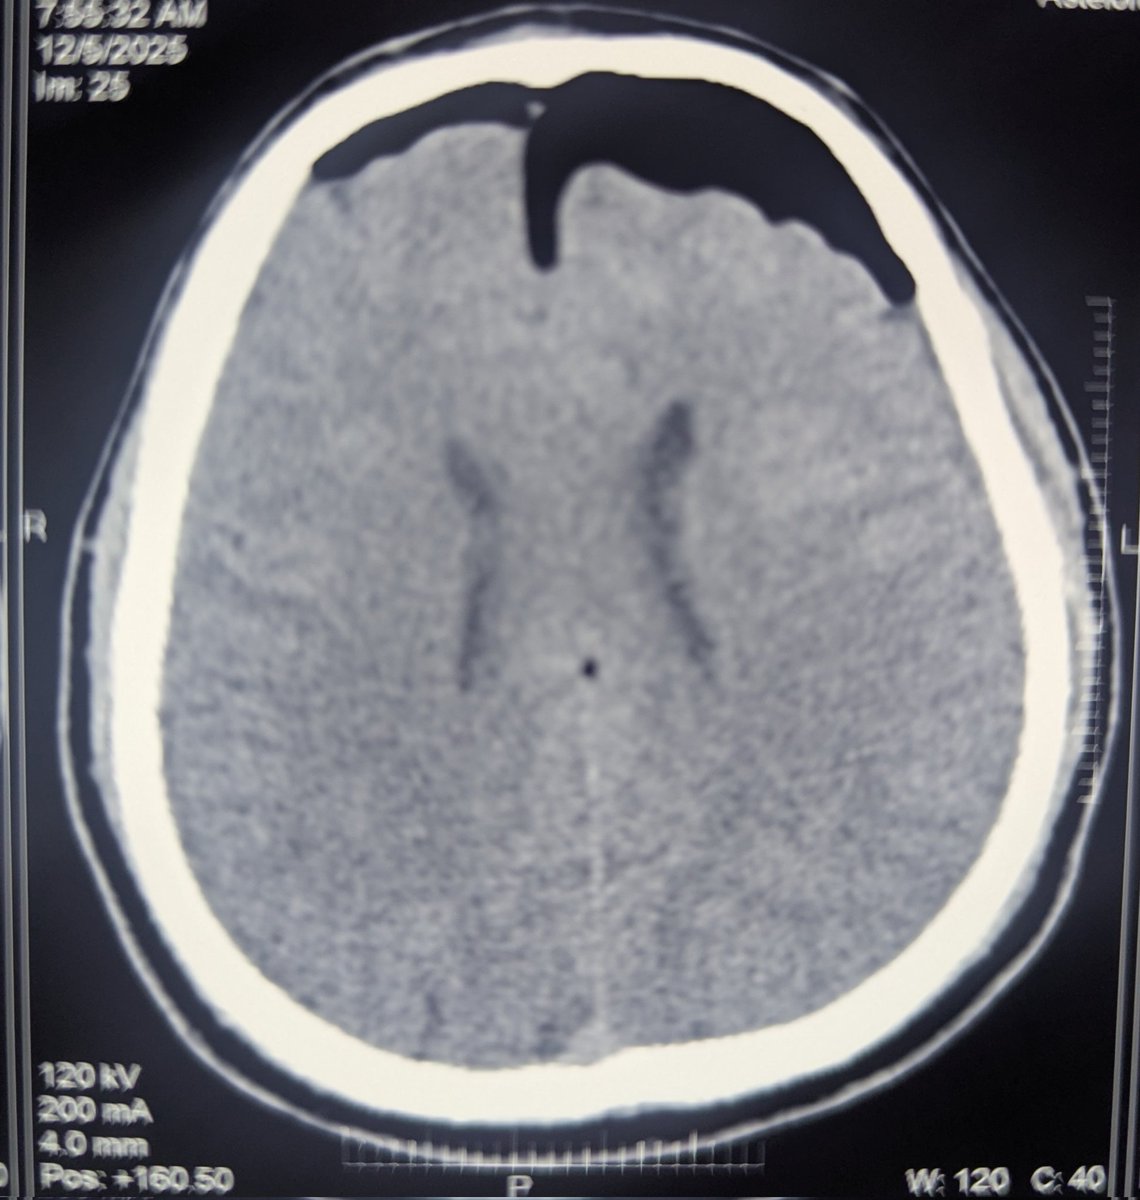

28 Male Head-on collision of two wheeler with lorry. No helmet. CT: Pneumocephalus Intraventricular hemorrhage Fracture of almost every facial bone Fracture ribs. No hemo, pneumothorax Liver lacerations. AAST 4. On receiving in the ICU, E4M6 Vitals stable Mouth opening